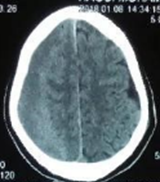

A 57 year old male with past history of mild traumatic brain injury a month ago presented to the emergency neurosurgery department with progressive headache and consciousness disturbance. The neurological examination revealed gait disturbance and left hemiparesis. Brain computed tomography revealed a bilateral chronic subdural hematoma, more predominant on the right fronto-parieto occipital convexity (Figure 1). Routine blood test were within normal limit. A right burr-hole drainage was performed with excellent neurologic recovery in the immediate post-operative period. A week later, the patient symptom reappeared, with a right hemiparesis this time. A stat Brain CT scan disclosed a complete resolution of the right sided hematoma but an increase in the left SDH with a fluid level (Figure 2). A hematologic consult suggested a complete blood coagulation work up that revealed increased D-Dimers and DIC. The patient received FFP and a left sided burr hole drainage was performed with good resolution of symptoms. However, recurrent headache with dizziness appeared 3 days after we removed the drain tube for testing. Repeat brain CT scan revealed reaccumulation of subdural hematoma on both side. The patient was again taken to the Operative room and bilateral subdural space aspiration was performed through both previous holes and the drain were left on both side for 5 days.